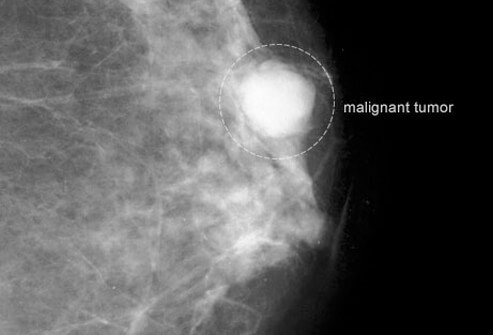

Catch Breast Cancer Early

Early Detection Saves Lives

Breast cancer is most treatable when caught in the earliest stages. In general, the smaller the tumor, the less likely it is to spread to organs or lymph nodes. The American Cancer Society recommends that women in their 20s and 30s have a clinical breast exam (CBE) by a health-care professional about every 3 years and an exam every year for women 40 years of age and over. A clinical breast exam does not replace breast cancer screening by mammography.

What About Mammograms?

Guidelines Have Changed

Mammography is a low-dose X-ray test that may help find a small malignancy at the earliest stages when it is still very treatable. The American Cancer Society (ACS) recommends a baseline mammogram for all women by age 40 and yearly mammograms for women 40 and older for as long as they are in good health.

In certain women (those with "lumpy breasts" or breast symptoms, or women with a high risk of developing breast cancer,) sometimes a baseline or first mammogram at 35 years of age is recommended. However, the U.S. Preventive Services Task Force (USPSTF) recommends against routine mammography screening for women before 50 years of age and suggests that screening end at 74 years of age. The USPSTF suggests that women between the ages of 50 and 74 have a mammogram every 2 years. Women who have certain risk factors for breast cancer may be advised to follow a different health screening schedule.